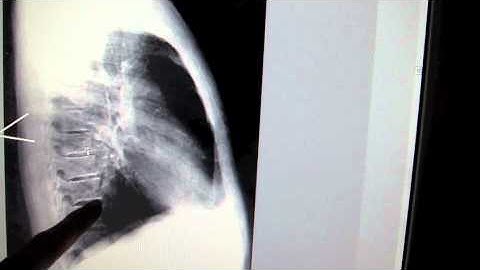

Lateral CXR path part 2 - "EM in 5"